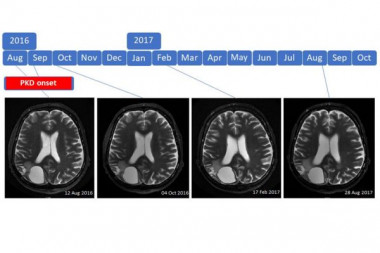

Introduction: Prognosis for patients with high-grade brain tumor is poor and survival did neither substantially change with advances in chemotherapy, radiotherapy and molecular profiling. Ketogenic diets have been suggested as a promising alternative therapy.